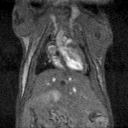

MRI is a complementary method to bioluminescence imaging in the detection of tumors allowing more precise assessment of the location and extent of orthotopic tumors (here an orthotopic model of prostate bone marrow metastasis).

MRI is a complementary method to bioluminescence imaging in the detection of tumors, allowing a more precise assessment of the location and extent of orthotopic tumors (here, an orthotopic model of prostate bone marrow metastasis). Image Credit: Scintica Instrumentation Inc